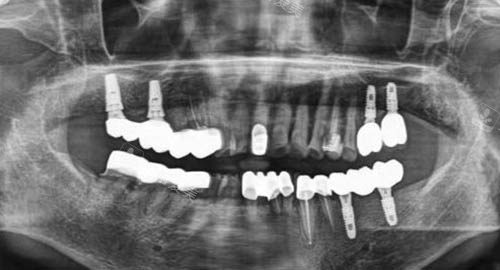

多颗牙齿种植ct

三、种牙和矫正技术有哪些特色?

在种植牙方面,曹春妮口腔诊所采用小创口不痛种植技术,大大减少患者的不适感。

诊所引进多种国内外出名种植系统,可根据患者骨质条件、口腔状况等选择比较适合的种植方案。

种植过程精密靠谱,术后修养快,种植牙使用寿命长。